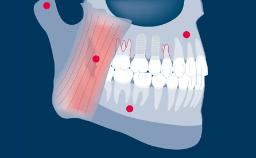

Quando os implantes são instalados e restaurados com as próteses finais, alguns princípios devem ser seguidos para obter um bom ajuste e sucesso a longo prazo da prótese. Os princípios gerais para a entrega de uma prótese implantossuportada são muito semelhantes àqueles para a entrega de uma prótese suportada por dente. No entanto, a complexidade é maior quando se utilizam próteses implantossuportadas, uma vez que elas podem ter múltiplos componentes que se encaixam muito precisamente ao longo de caminhos limitados de inserção. Além disso, essas próteses precisam ser entregues em implantes rigidamente fixados. Todos esses fatores tornam isso um procedimento muito mais rigoroso. Portanto, é importante ter um protocolo para garantir que as etapas corretas sejam seguidas, a fim de minimizar o risco de complicações e de poder verificar se o procedimento foi realizado corretamente. Também é importante poder fornecer informações de linha de base sobre a prótese contra as quais você pode comparar a condição ao longo do tempo.

- descrever os passos da prova e verificar se uma prótese é clinicamente aceitável